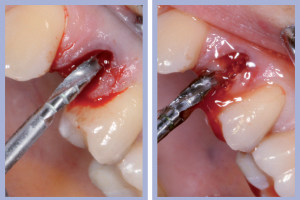

- Figg. 9a, b – Preparazione del sito di destra

- Figg. 10a, b – Preparazione del sito di sinistra

Dopo l’estrazione, eseguita con i consueti passaggi di scollamento-lussazione-estrazione, la revisione chirurgica tramite cucchiaio alveolare consentiva la completa rimozione dei frustoli di tessuto di granulazione e di legamento parodontale residuo. La preparazione del sito implantare veniva effettuata con approccio flapless, ovvero senza l’esecuzione del lembo.

Una volta determinato, sul versante palatale dell’alveolo, il giusto asse di preparazione, si lavorava fino alla profondità programmata; la sequenza di frese comunemente impiegate per il diametro implantare da posizionare completava la preparazione dell’alveolo chirurgico. Non era richiesto l’uso della fresa svasatrice dal momento che a livello cervicale l’alveolo presentava un diametro maggiore di quello implantare.